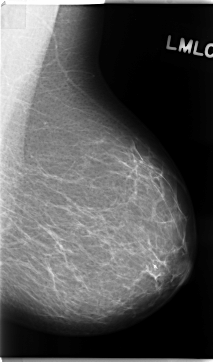

ics_version 1.0 filename C-0131-1 DATE_OF_STUDY 22 9 1995 PATIENT_AGE 48 FILM FILM_TYPE REGULAR DENSITY 1 DATE_DIGITIZED 16 1 1998 DIGITIZER LUMISYS LASER SEQUENCE LEFT_CC LINES 4776 PIXELS_PER_LINE 2712 BITS_PER_PIXEL 12 RESOLUTION 50 NON_OVERLAY LEFT_MLO LINES 4696 PIXELS_PER_LINE 2760 BITS_PER_PIXEL 12 RESOLUTION 50 NON_OVERLAY RIGHT_CC LINES 4736 PIXELS_PER_LINE 2616 BITS_PER_PIXEL 12 RESOLUTION 50 OVERLAY RIGHT_MLO LINES 4704 PIXELS_PER_LINE 2720 BITS_PER_PIXEL 12 RESOLUTION 50 OVERLAY |